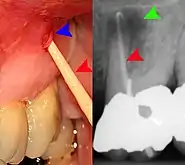

Transillumination demonstrating fracture Decay (green) with apical abscess (blue)

Decay (green) with apical abscess (blue) Gutta-percha point indicating abscess origin

Gutta-percha point indicating abscess origin